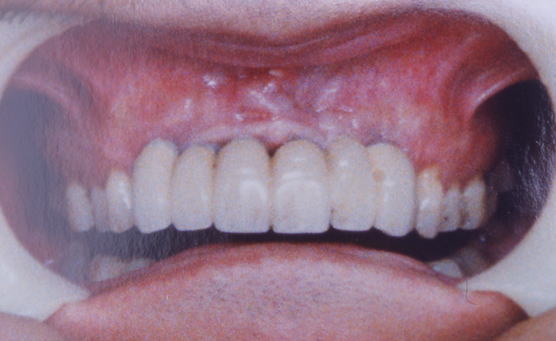

症例101